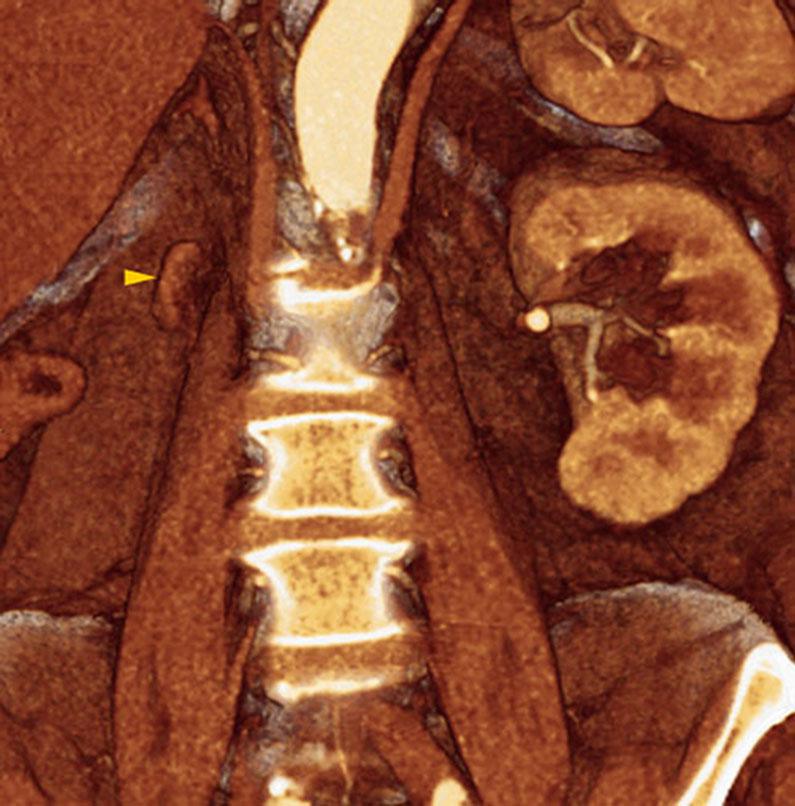

Agenesia Renal